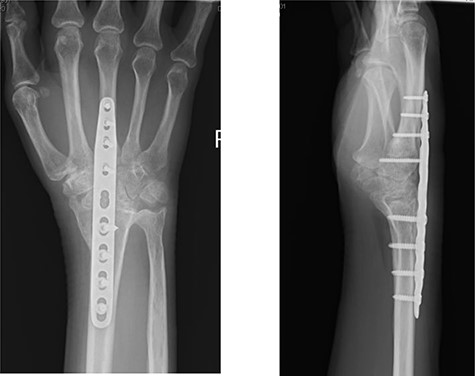

A 50-year-old, right-hand-dominant woman, presented with a history of stiffness and pain affecting her right wrist, associated with a history of increasing swelling on its palmar aspect. She had been treated for post-traumatic arthritis of the same wrist 7 months earlier by arthroplasty with a Pyrocarbon Amandys implant; she also reported gradual onset of tingling sensations in her ring finger. She had an initial uneventful recovery but developed clinical symptoms of carpal tunnel syndrome 2 months later, with paresthesia in the right thumb and index finger radiating to the forearm, which was worse at night. A diagnosis of carpal tunnel syndrome was confirmed by nerve conduction studies. Post-operative radiograph at this time showed the pyrocarbon implant in an adequate position (Fig. 1).

Radiographs demonstrated that the Pyrocarbon implant was palmarly displaced and rotated 90 degrees; it had migrated into the carpal tunnel/ distal forearm (Fig. 2). The clinical diagnosis was compression of the ulnar due to the migration of implant. Surgery was carried out 1 month later during which the Pyrocarbon Amandys wrist implant was removed through a volar approach (Fig. 3) and total wrist fusion was performed using a straight Arbeitsgemeinschaft für Osteosynthesefragen (AO) wrist fusion plate (Fig. 4). The surgery successfully relieved all wrist pain and was accompanied by prompt resolution of symptoms of ulnar nerve compression; she was discharged from follow-up approximately 3 months after surgery.

X-rays of the right hand showed palmar displacement of the pyrocarbon implant.

Post-operative radiographs following removal of pyrocarbon implant and total wrist fusion.